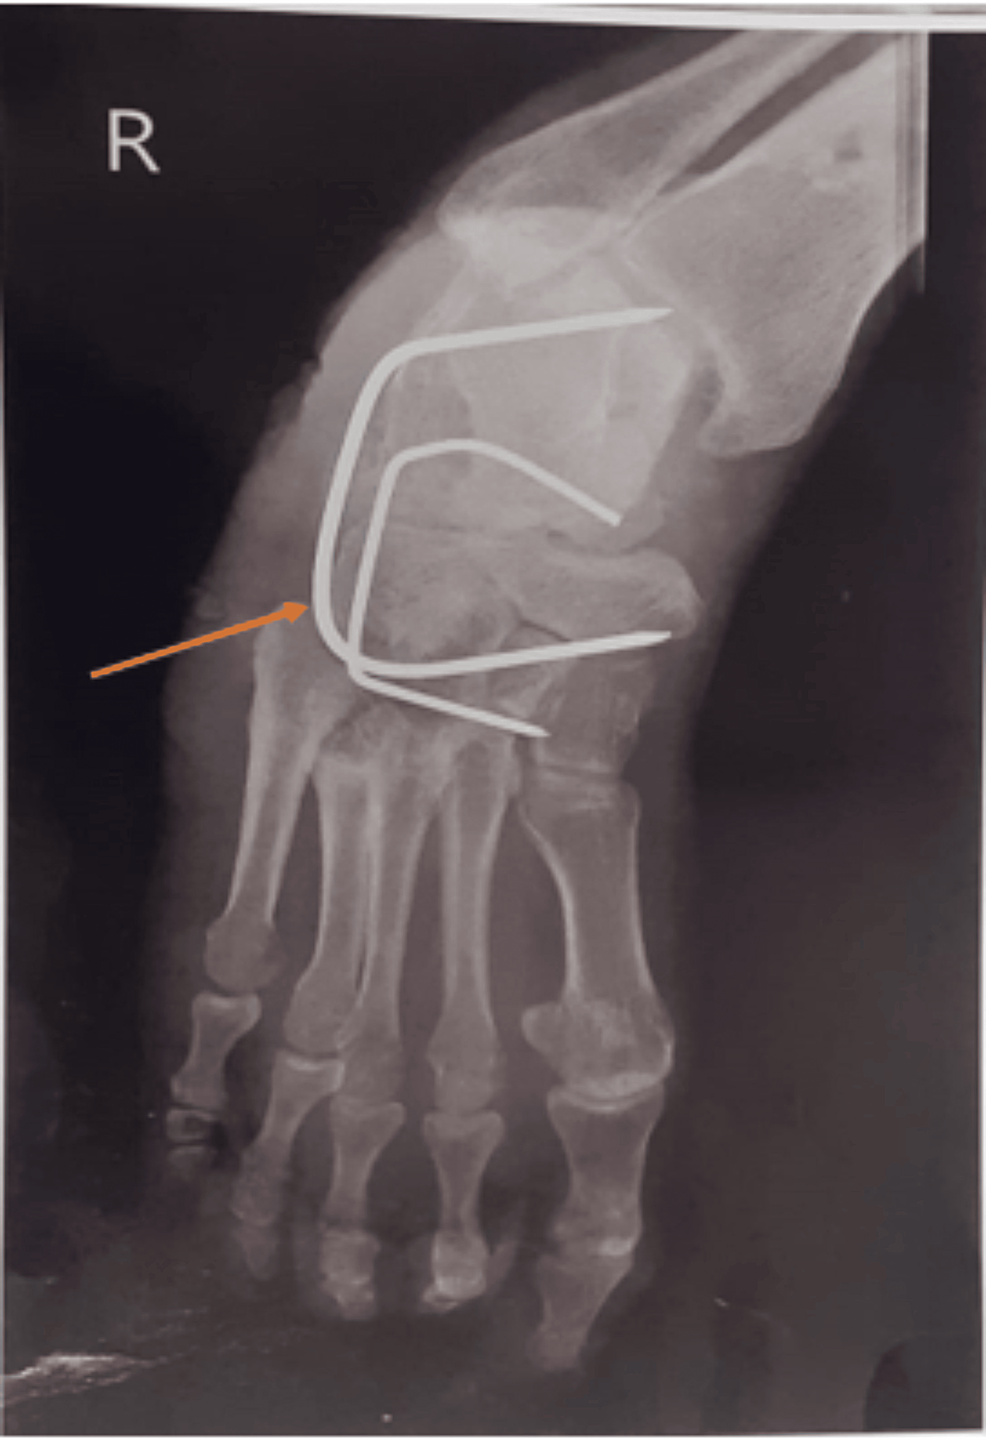

Hindfoot equinus deformity. Lateral standing foot radiograph in a Orthotics For Equinus Deformity equinus plays an important role in flatfoot deformity. orthotics are lower extremity supportive apparel that provide soft tissue protection, bone/joint stability and control of body segment motion. to diagnose equinus, the foot and ankle surgeon will evaluate the ankle's range of motion when the knee is flexed (bent) as well as extended (straightened). equinus deformity is. Orthotics For Equinus Deformity.